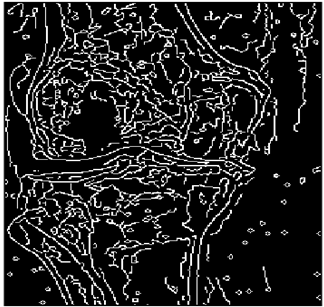

Table 12. Edge-detected image of “X-ray 3” after binarization for different noises.

NoiseCannyStandardSmooth

No noise Mathematics 10 02421 i114 Mathematics 10 02421 i115 Mathematics 10 02421 i116

G(0.001) Mathematics 10 02421 i117 Mathematics 10 02421 i118 Mathematics 10 02421 i119

G(0.002) Mathematics 10 02421 i120 Mathematics 10 02421 i121 Mathematics 10 02421 i122

G(0.003) Mathematics 10 02421 i123 Mathematics 10 02421 i124 Mathematics 10 02421 i125

I(0.25%) Mathematics 10 02421 i126 Mathematics 10 02421 i127 Mathematics 10 02421 i128

I(0.5%) Mathematics 10 02421 i129 Mathematics 10 02421 i130 Mathematics 10 02421 i131

I(1%) Mathematics 10 02421 i132 Mathematics 10 02421 i133 Mathematics 10 02421 i134

For Table 11, Table 12 and Table 13, the same points of Table 10 can be made. Therefore, for the sake of brevity, the points are not mentioned.